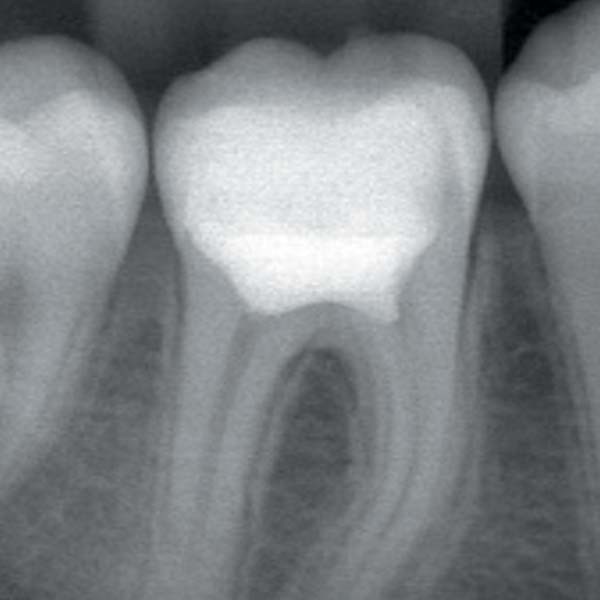

La pulpotomie a longtemps été considérée en odontologie pédiatrique comme une solution intermédiaire d’attente. Utilisée pour traiter des dents immatures sur lesquelles le traitement canalaire est complexe, la pulpotomie camérale permet de conserver la vitalité pulpaire nécessaire à la poursuite de la radiculogenèse et sa finition par l’apexogenèse.

Le terme « apexogenèse » renvoie à une notion biologique et non thérapeutique. L’apexogenèse est le processus de développement dentaire qui conduit à la fermeture apicale de la dent et à la mise en place de son apex (apexogenèse) qui fait passer la dent d’un stade « immature » au stade de « mature ». Une fois cette maturité acquise après traitement par pulpotomie camérale, le praticien se sent très souvent en confiance pour réaliser le traitement canalaire, et réintervient alors pour réaliser la pulpectomie de la dent.

Sur le plan biologique, la logique voudrait qu’on ne réintervienne pas sur cette dent. Si la radiculogenèse et l’apexogenèse ont pu se mettre en place, c’est bien que la pulpe est vivante, et en bonne santé. Si l’étanchéité coronaire est observée, que pourrait-il lui arriver ensuite, qui pourrait justifier d’éliminer ce tissu biologique et le remplacer par un matériau inerte et synthétique ?

Depuis quelques années, l’intérêt de la pulpotomie camérale comme thérapeutique permanente sur la dent adulte est ressuscité de ses cendres. Souvent considéré comme traitement de seconde zone, force est de constater que les nombreuses études cliniques réalisées sur le sujet tendent toutes à démontrer la pertinence de traiter une dent dont la pulpe est exposée, voire inflammatoire, par un coiffage profond, au niveau des entrées canalaires.

La pulpotomie camérale peut s’intégrer à ce titre comme une étape supplémentaire des traitements dentaires disponibles pour la conservation d’une dent. Elle vient s’insérer entre le coiffage pulpaire, dont le pronostic reste difficile à anticiper, et le traitement canalaire, considéré comme invasif et mutilant quand l’indication n’est pas clairement justifiée.